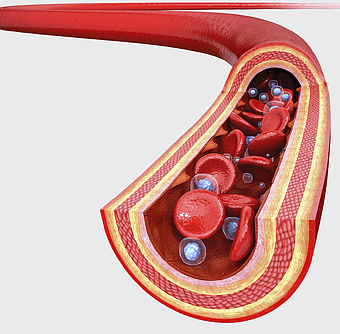

blood vessel illustration, artery drawing, red blood cells, leukocytes, vascular health, circulatory system, blood flow dynamics -

Red blood cell, White blood cell, donation blood, blood vessel, circulatory system, medical illustration, blood components -

red blood cells, white blood cell, platelets under microscope, blood cell granule, human circulatory system, microscopic view of hemoglobin, cellular blood components -

red blood cell illustration, platelet-rich plasma therapy, mean platelet volume test, complete blood count results, blood cell structure, hematopoiesis process, erythrocyte function -

hemoglobin oxygen transport, venous thrombosis symptoms, iron in blood cells, red blood cell function, circulatory system health, blood gas exchange process, cardiovascular health illustration -